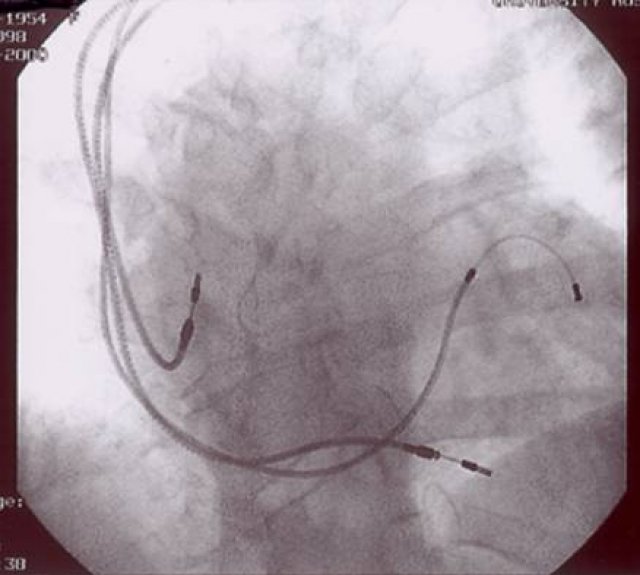

- AICD (Defibrillator): Bei tödlichem Herzrasen sorgt dieser Schrittmacher mittels sofortiger Überstimulation oder Elektroschock für das Überleben des Patienten.

- CRT-Systeme: Die Schrittmacher mit 2-Kammer-Stimulation verbessern bei Patienten mit Linksschenkelblock und stark geschwächter Herztätigkeit die Leistungsfähigkeit.